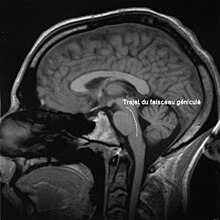

Le faisceau cortico-bulbaire relie le cortex moteur aux noyaux, origines des nerfs crâniens, dans le tronc cérébral. Dans son chemin, il traverse le genou de la capsule interne, ce qui lui vaut le qualificatif de « géniculé ».